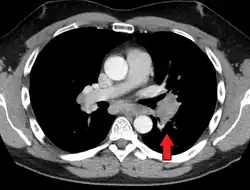

CT scan of the chest showing lymphadenopathy (arrows) in the mediastinum due to sarcoidosis

Diagnosis of sarcoidosis is a matter of exclusion, as there is no specific test for the condition. To exclude sarcoidosis in a case presenting with pulmonary symptoms might involve a chest radiograph, CT scan of chest, PET scan, CT-guided biopsy, mediastinoscopy, open lung biopsy, bronchoscopy with biopsy, endobronchial ultrasound, and endoscopic ultrasound with fine-needle aspiration of mediastinal lymph nodes (EBUS FNA). Tissue from biopsy of lymph nodes is subjected to both flow cytometry to rule out cancer and special stains (acid fast bacilli stain and Gömöri methenamine silver stain) to rule out microorganisms and fungi.[91][92][12][93]